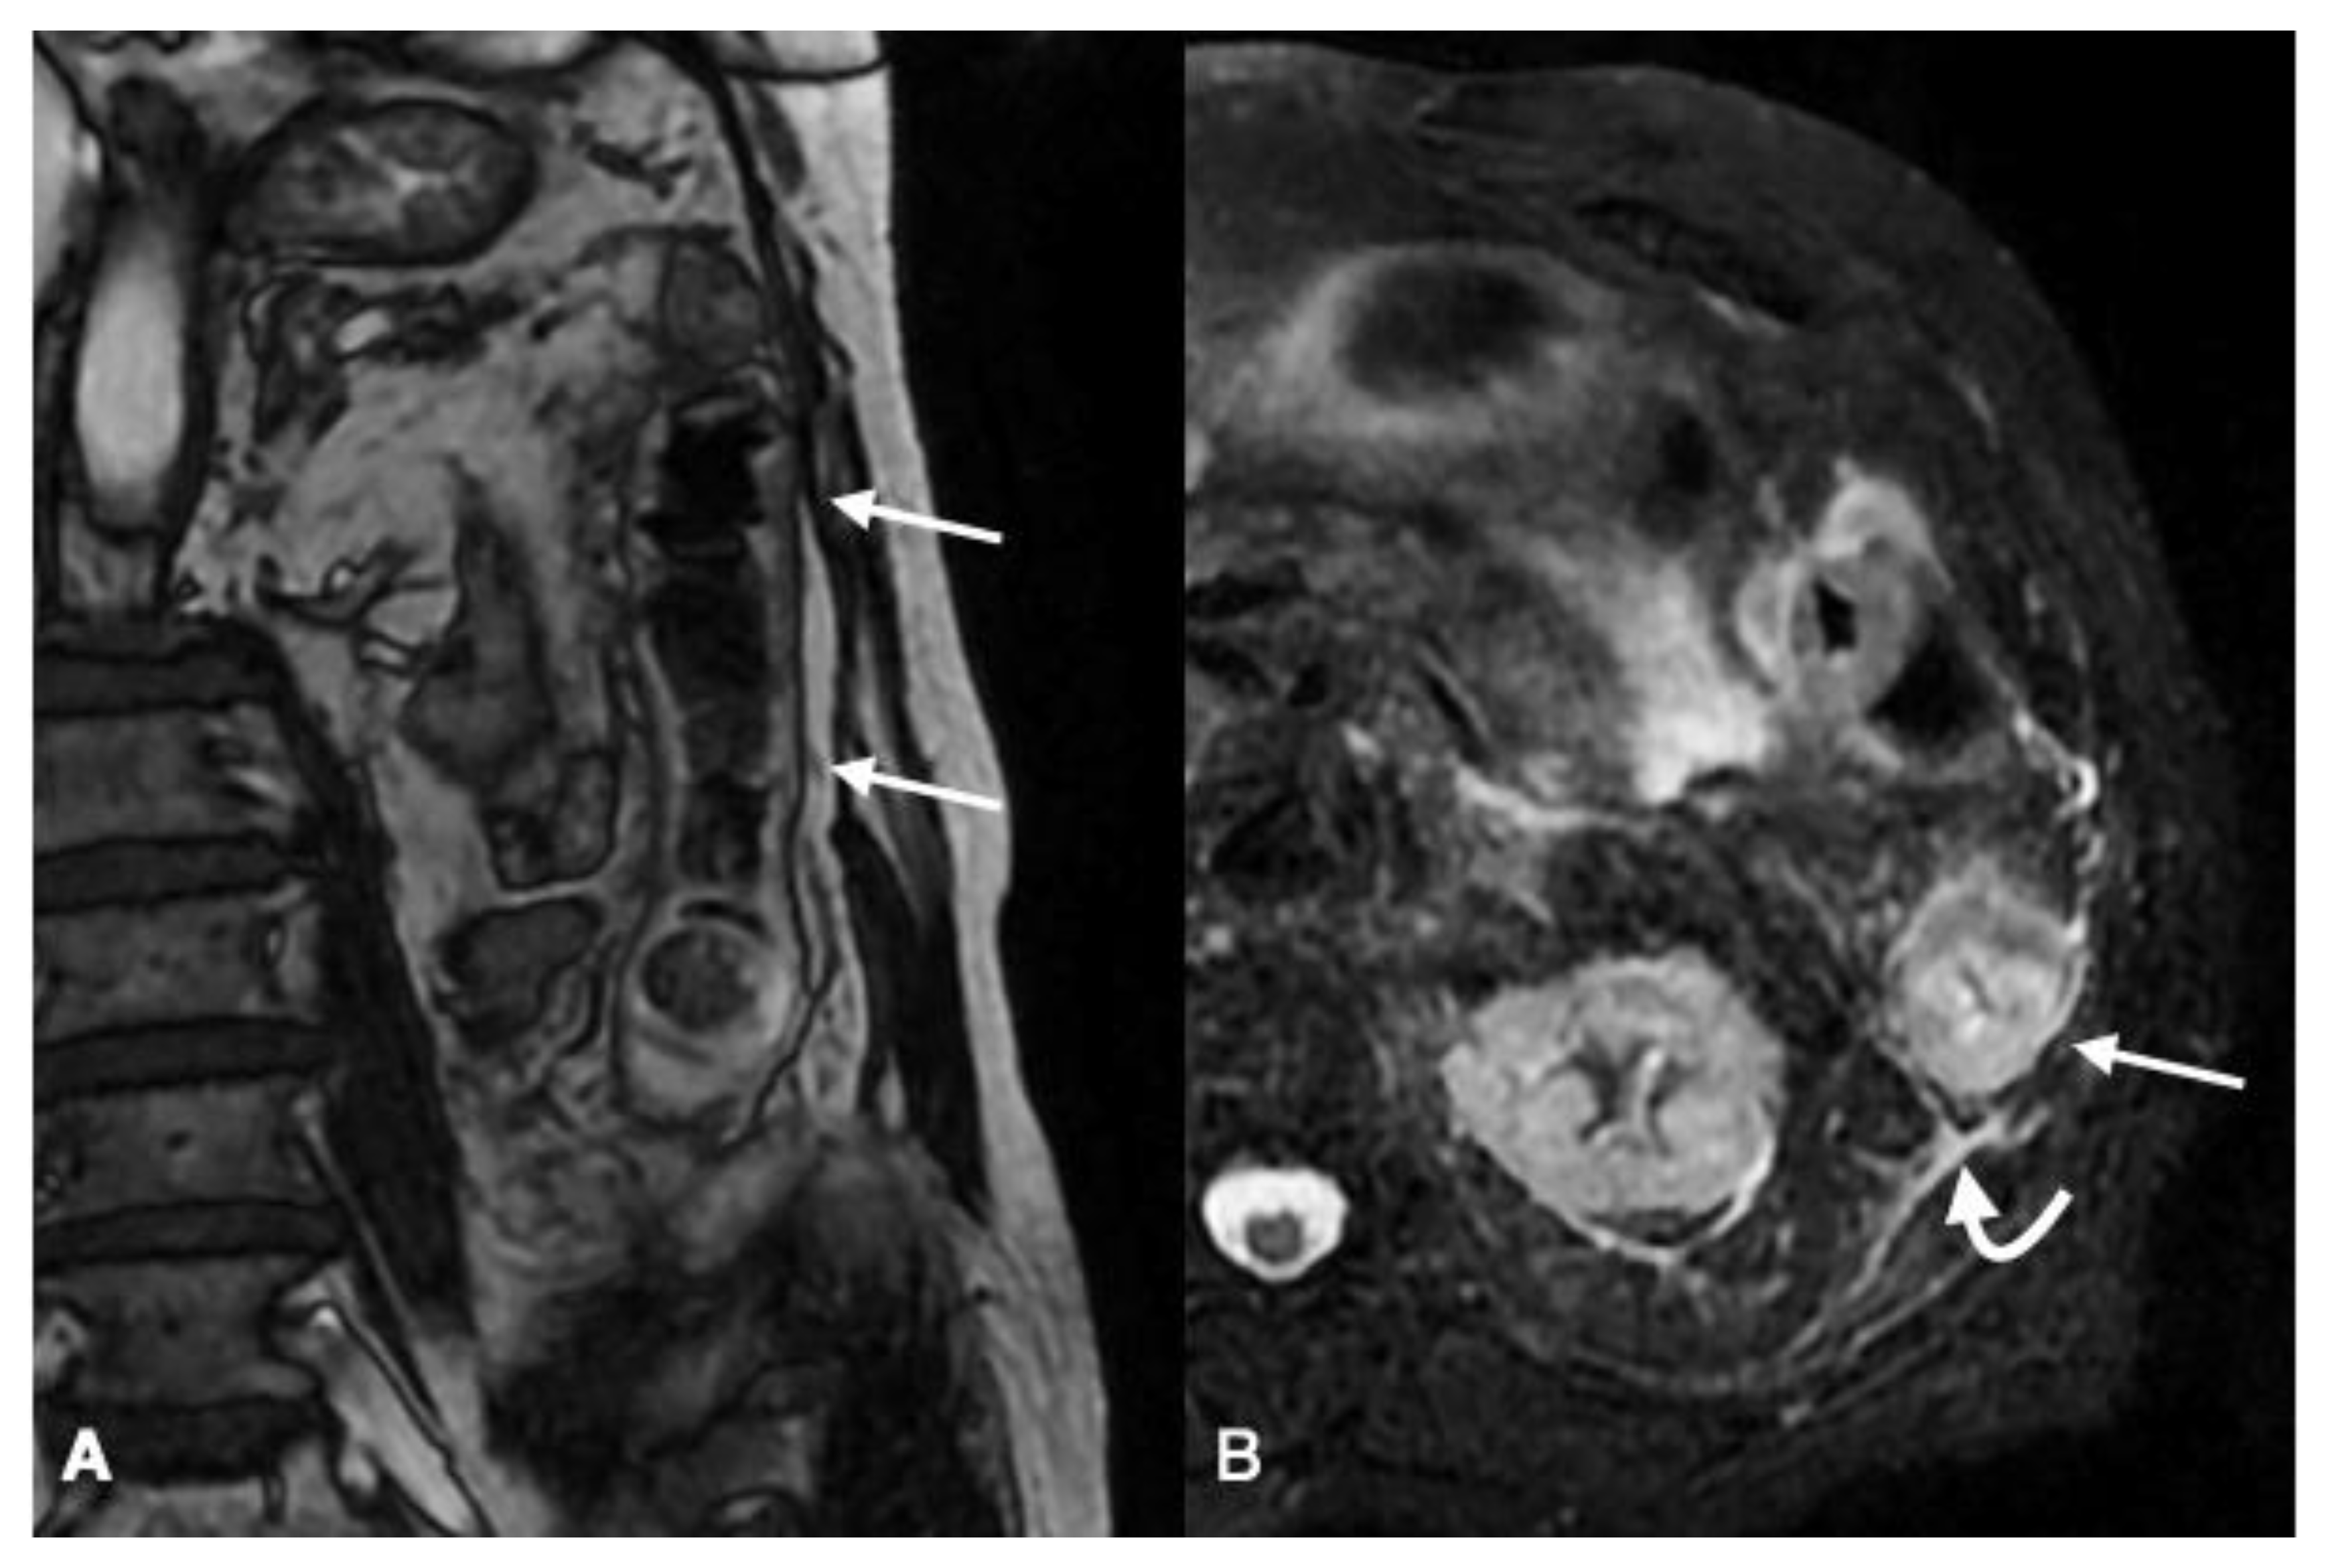

4.2.4. MRI

Imaging Technique

Imaging Findings

- Iacobellis, F.; Berritto, D.; Somma, F.; Cavaliere, C.; Corona, M.; Cozzolino, S.; Fulciniti, F.; Cappabianca, S.; Rotondo, A.; Grassi, R. Magnetic resonance imaging: A new tool for diagnosis of acute ischemic colitis? World J. Gastroenterol. 2012, 18, 1496–1501. [Google Scholar] [CrossRef]

- Berritto, D.; Iacobellis, F.; Somma, F.; Corona, M.; Faggian, A.; Iacomino, A.; Feragalli, B.; Saba, L.; La Porta, M.; Grassi, R. 7T mMR in the assessment of acute arterial mesenteric ischemia in a rat model. J. Biol. Regul. Homeost. Agents 2013, 27, 771–779. [Google Scholar]

- Somma, F.; Berritto, D.; Iacobellis, F.; Landi, N.; Cavaliere, C.; Corona, M.; Russo, S.; Di Mizio, R.; Rotondo, A.; Grassi, R. 7T μMRI of mesenteric venous ischemia in a rat model: Timing of the appearance of findings. Magn. Reson. Imaging 2013, 31, 408–413. [Google Scholar] [CrossRef] [PubMed]

- Berritto, D.; Somma, F.; Landi, N.; Cavaliere, C.; Corona, M.; Russo, S.; Fulciniti, F.; Cappabianca, S.; Rotondo, A.; Grassi, R. Seven-Tesla micro-MRI in early detection of acute arterial ischaemia: Evolution of findings in an in vivo rat model. Radiol. Med. 2011, 116, 829–841. [Google Scholar] [CrossRef]